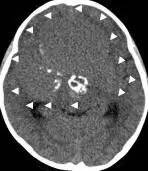

病例二:患儿女性,7岁,主因头痛2年,精神差1个月收入院。入院时头CT见典型的“超大型”颅咽管瘤,直径约9厘米,见图6。

图6.CT显示囊性颅咽管瘤

白色三角显示肿瘤边界